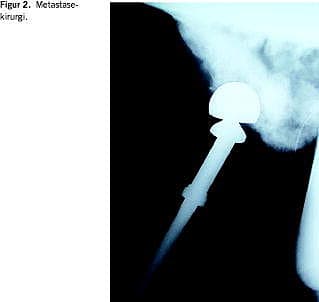

Udviklingen af bedre teknikker inden for ekstremitetsbevarende tumorkirurgi, protesekirurgi, traumekirurgi og degenerative ryglidelser har kunnet overføres til metastasekirurgi [7]. Dette har sammen med tiltagende brug af præoperativ tumorembolisering og bedre anæstesimetoder øget mulighederne for rekonstruktiv kirurgi ved patologiske frakturer og behandling af truende paraplegi og inkontinens fra spinalkompression pga. knoglemetastaser. For at sikre stabiliteten bruges der i stigende omfang proteser ved lednære metastaser og marvsøm i rørknogler (Figur 2 ). Opfyldning af metastasekaviteten med knoglecement kan øge stabiliteten. Skinneosteosyntese må betragtes som obsolet. Inden for rygkirurgien er der tendens til mere radikal tumorfjernelse og stabilisering end tidligere.

Kirurgisk behandling af metastaser i bækken og underekstremiteter medfører, at 90% af patienterne kan gå - med eller uden krykker - efter seks måneder [8]. Brug af protese ved metastaser i den proksimale femur synes at bedre mobiliteten i forhold til intern fiksering. Operation synes at reducere morfikaforbruget seks måneder efter operation [8]. Brug af proteser ved lednære metastaser i overekstremiteter synes at give en bedre smertelindring end brug af intern fiksering [9]. Kirurgisk behandling synes at være mere effektiv end onkologisk behandling af rygmetastaser mht. bedring af smerte, mobilitet og inkontinens [10].